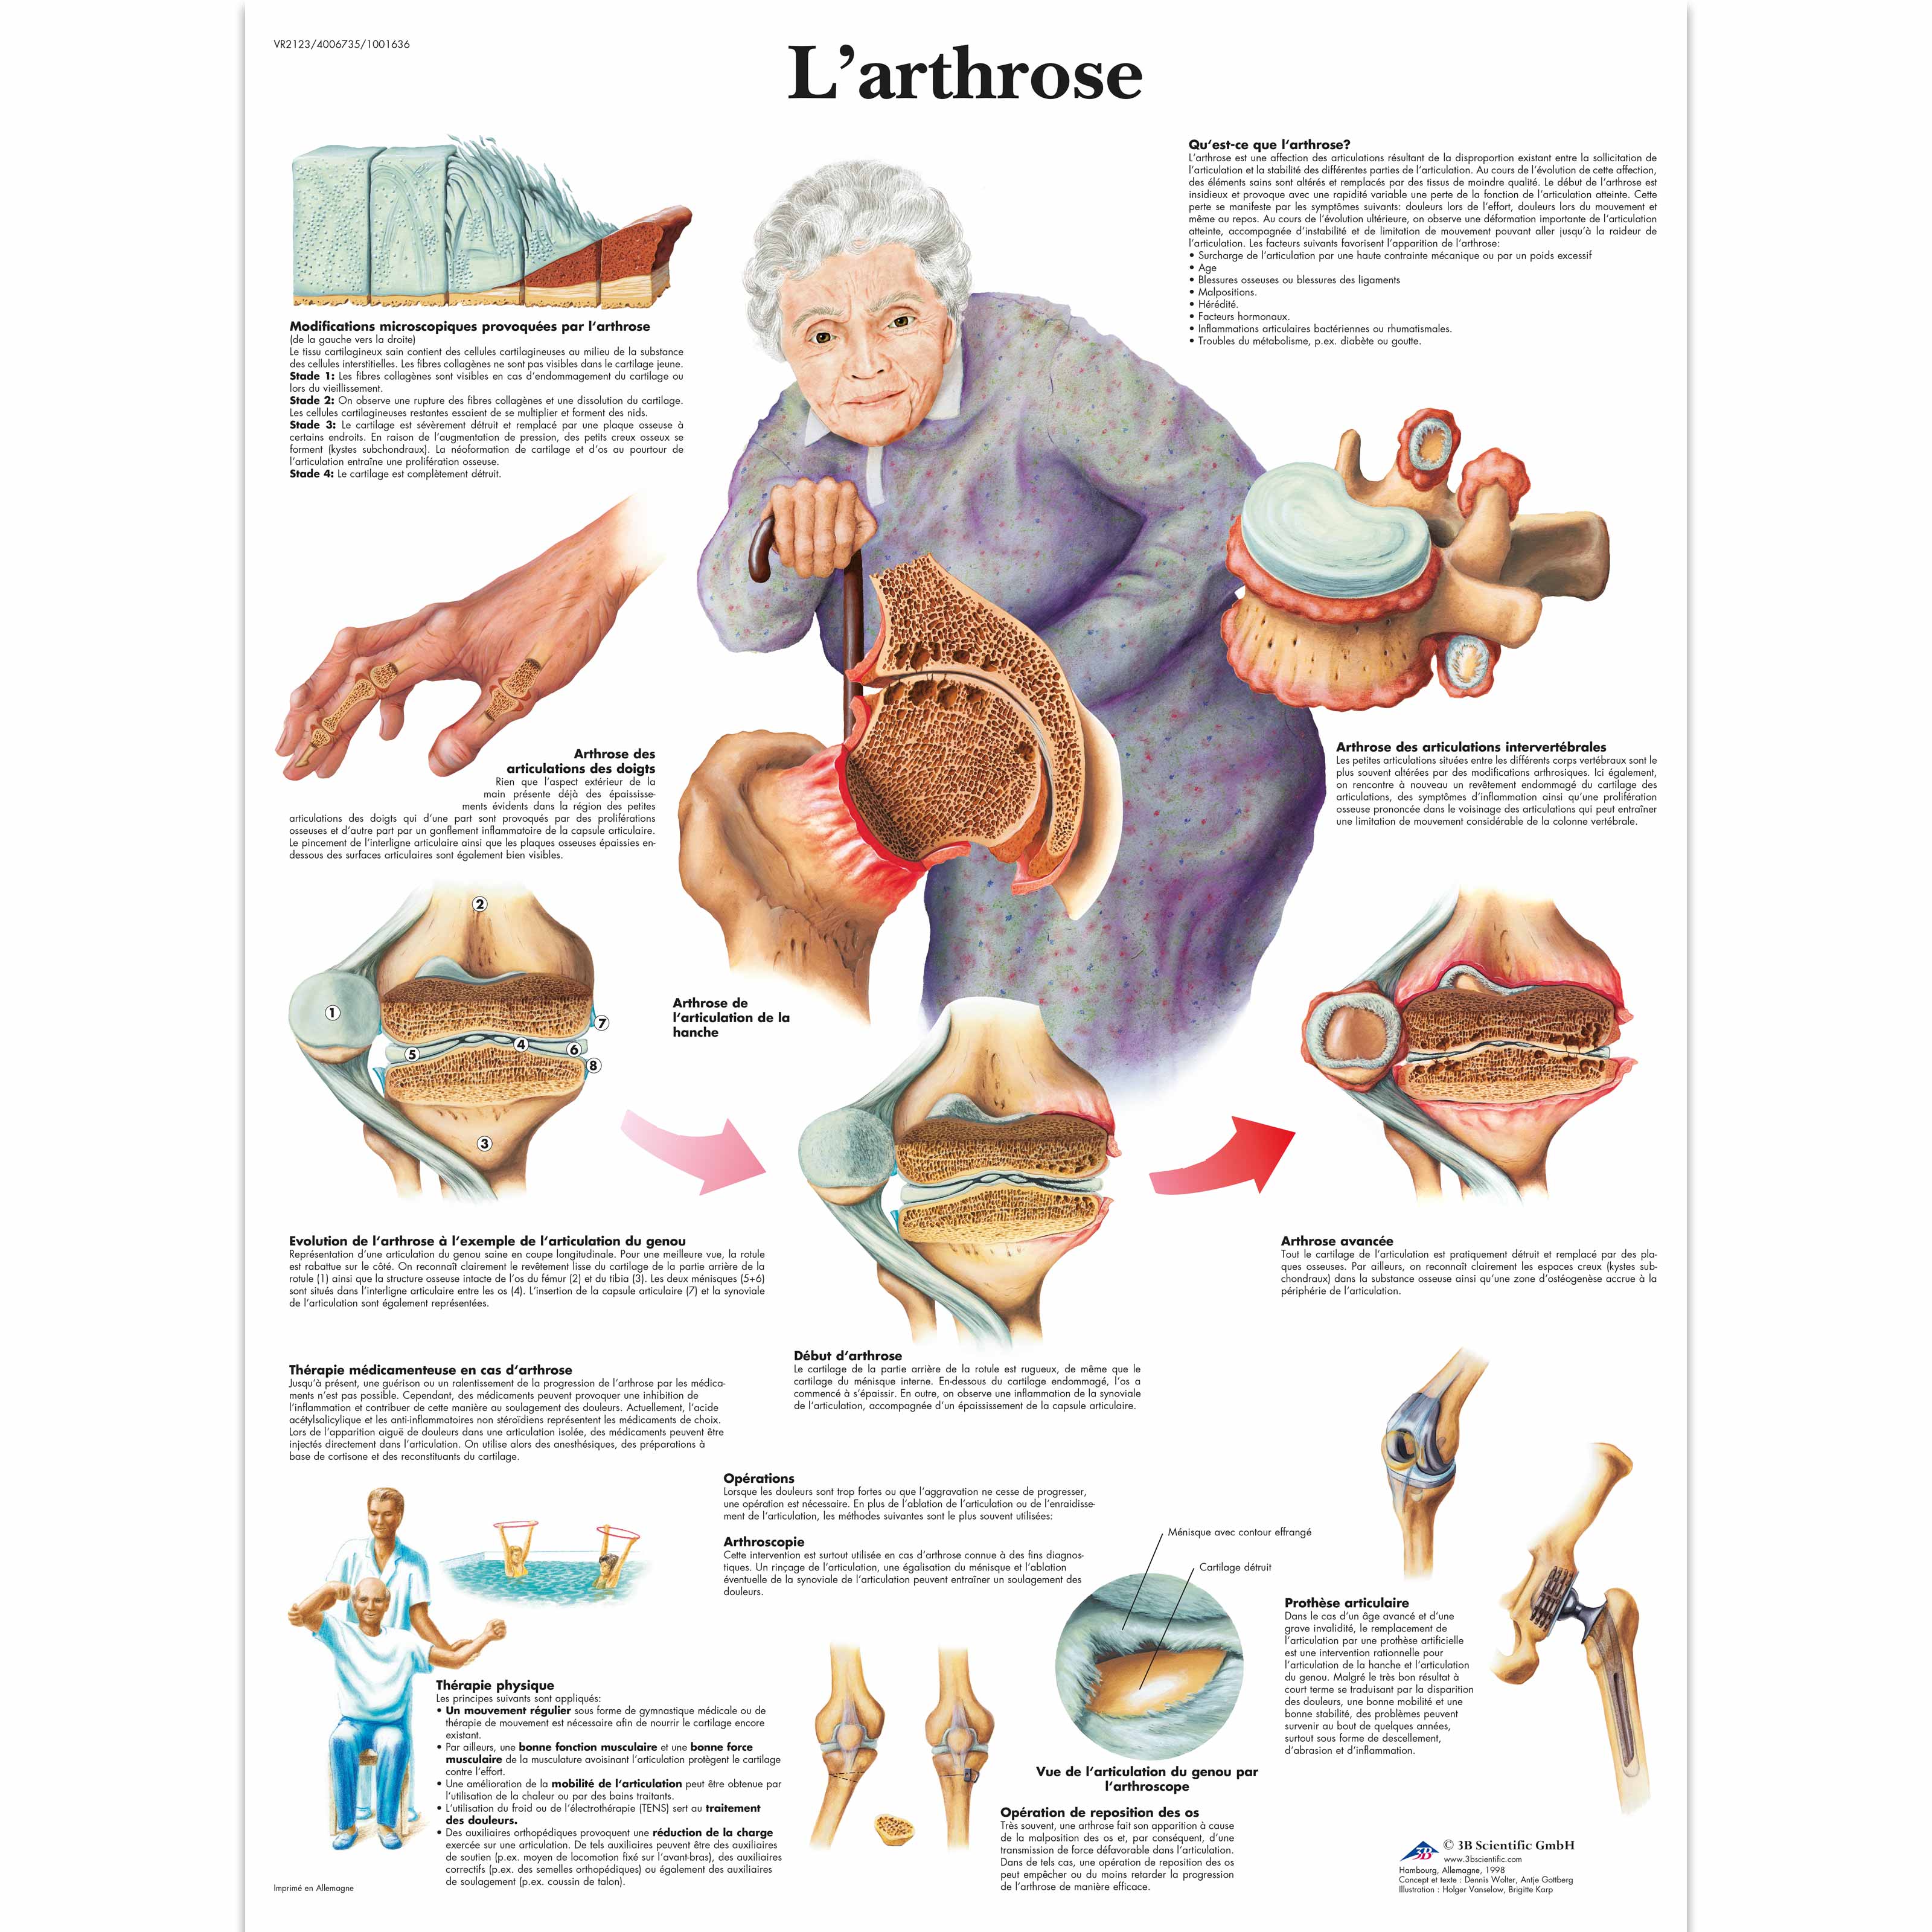

Définition : qu'est-ce que l'arthrose ? L’ arthrose est une destruction du cartilage qui tapisse les articulations. Ces crises durent quelques jours à quelques semaines et finissent par se calmer.

Arthrose acromio-claviculaire : symptômes. Tous les thèmes de santé. 5 - Des doigts .Pendant une poussée d’arthrose, les symptômes correspondent à une forte douleur à l’articulation touchée. D’autres symptômes peuvent s’y associer : – Raideur de la cheville ; – Œdèmes autour . L’érosion et l’inflammation provoquées par l’arthrose acromio-claviculaire peuvent engendrer des douleurs qui irradient vers la nuque et le trapèze. Par exemple, vous pouvez .comCombien de temps dure une crise d’arthrose ? | Arsylabarsylab. Cependant, des pistes existent.sur prescription médicale, la prise de médicaments antalgiques, anti-inflammatoires ou anti-arthrosiques peut être envisagée selon les cas. Les symptômes de l'arthrose du genou sont : La douleur et la gêne dans les mouvements du genou.25 octobre 2023.La zygarthrose ou arthrose zygapophysaire postérieure correspond à une arthrose ou une usure des cartilages dans les articulations inter-apophysaires .On comprend encore mal l’origine de l’arthrose, et l’on ignore encore comment limiter sa progression.Les articulations les plus souvent atteintes sont : les mains, les pieds, les genoux, les hanches; et les vertèbres.Vous apprendrez les exercices utiles à pratiquer en cas d’arthrose cervicale.Les symptômes comprennent un début progressif de la douleur articulaire, qui s'aggrave à la mise en charge ou avec la fatigue et qui est soulagée par le repos, et une raideur qui réduit l . Les symptômes de l’arthrite sont ressentis à . Les études montrent que le gingembre, le curcuma peuvent améliorer la douleur et la raideur matinale.Temps de Lecture Estimé: 6 min27 octobre 2023. Dans ce contexte, le diagnostic peut être posé . Outre l'usure du cartilage, on observe un durcissement de l'os sous-jacent, une croissance osseuse et des calcifications au mauvais endroit, une inflammation de la membrane . L’examen clinique, un bilan sanguin et radiologique . En dehors des poussées, il reste une douleur chronique. Les principaux symptômes de l’arthrose de hanche sont la douleur, la difficulté à marcher normalement et une série d’autres symptômes moins évidents.Le traitement de l'arthrite dentaire commence par le traitement de la cause. Tous ces changements rendent vos mouvements pénibles et les tâches quotidiennes plus difficiles à accomplir. Celle-ci est très fréquente et peut avoir diverses origines. Une ostéochondrite est une anomalie au niveau des zones de croissance des os et du cartilage. Les douleurs sont plus intenses au réveil, jusqu'à ce que les articulations s’échauffent, . Traitements médicaux.

Il peut s'agir soit de rétablir le bon équilibre dentaire en corrigeant un implant ou une prothèse mal adaptée, soit de soigner une carie, de réajuster l'appareil dentaire, ou de poser une gouttière en cas de mauvais contact ou bien encore en traitant la dent . Cette usure du cartilage touche souvent les femmes après 50 ans. La facilité et l'ampleur de vos mouvements ont diminué. Pour vous soulager pendant une poussée d’arthrose cervicale, le médecin peut vous proposer de porter une minerve en mousse durant quelques jours. Chez les personnes qui souffrent de rectocolite hémorragique, les rechutes sont définies comme la réapparition de selles glaireuses et sanguinolentes après une période sans symptômes. Au début les symptômes de l'arthrose de la cheville se manifestent surtout après un effort, puis sont soulagés au repos.Le premier symptôme de l’arthrose est la douleur, qui apparaît généralement lorsque l’articulation est mobilisée, et se calme dès qu’elle est mise au repos ; Cette douleur peut s .

Elle est la forme la plus courante de .Qu’est-ce que c’est? L'arthrose est une maladie dégénérative des articulations.Ils sont utilisés pour réduire les symptômes et permettre ainsi davantage d’activités quotidiennes.